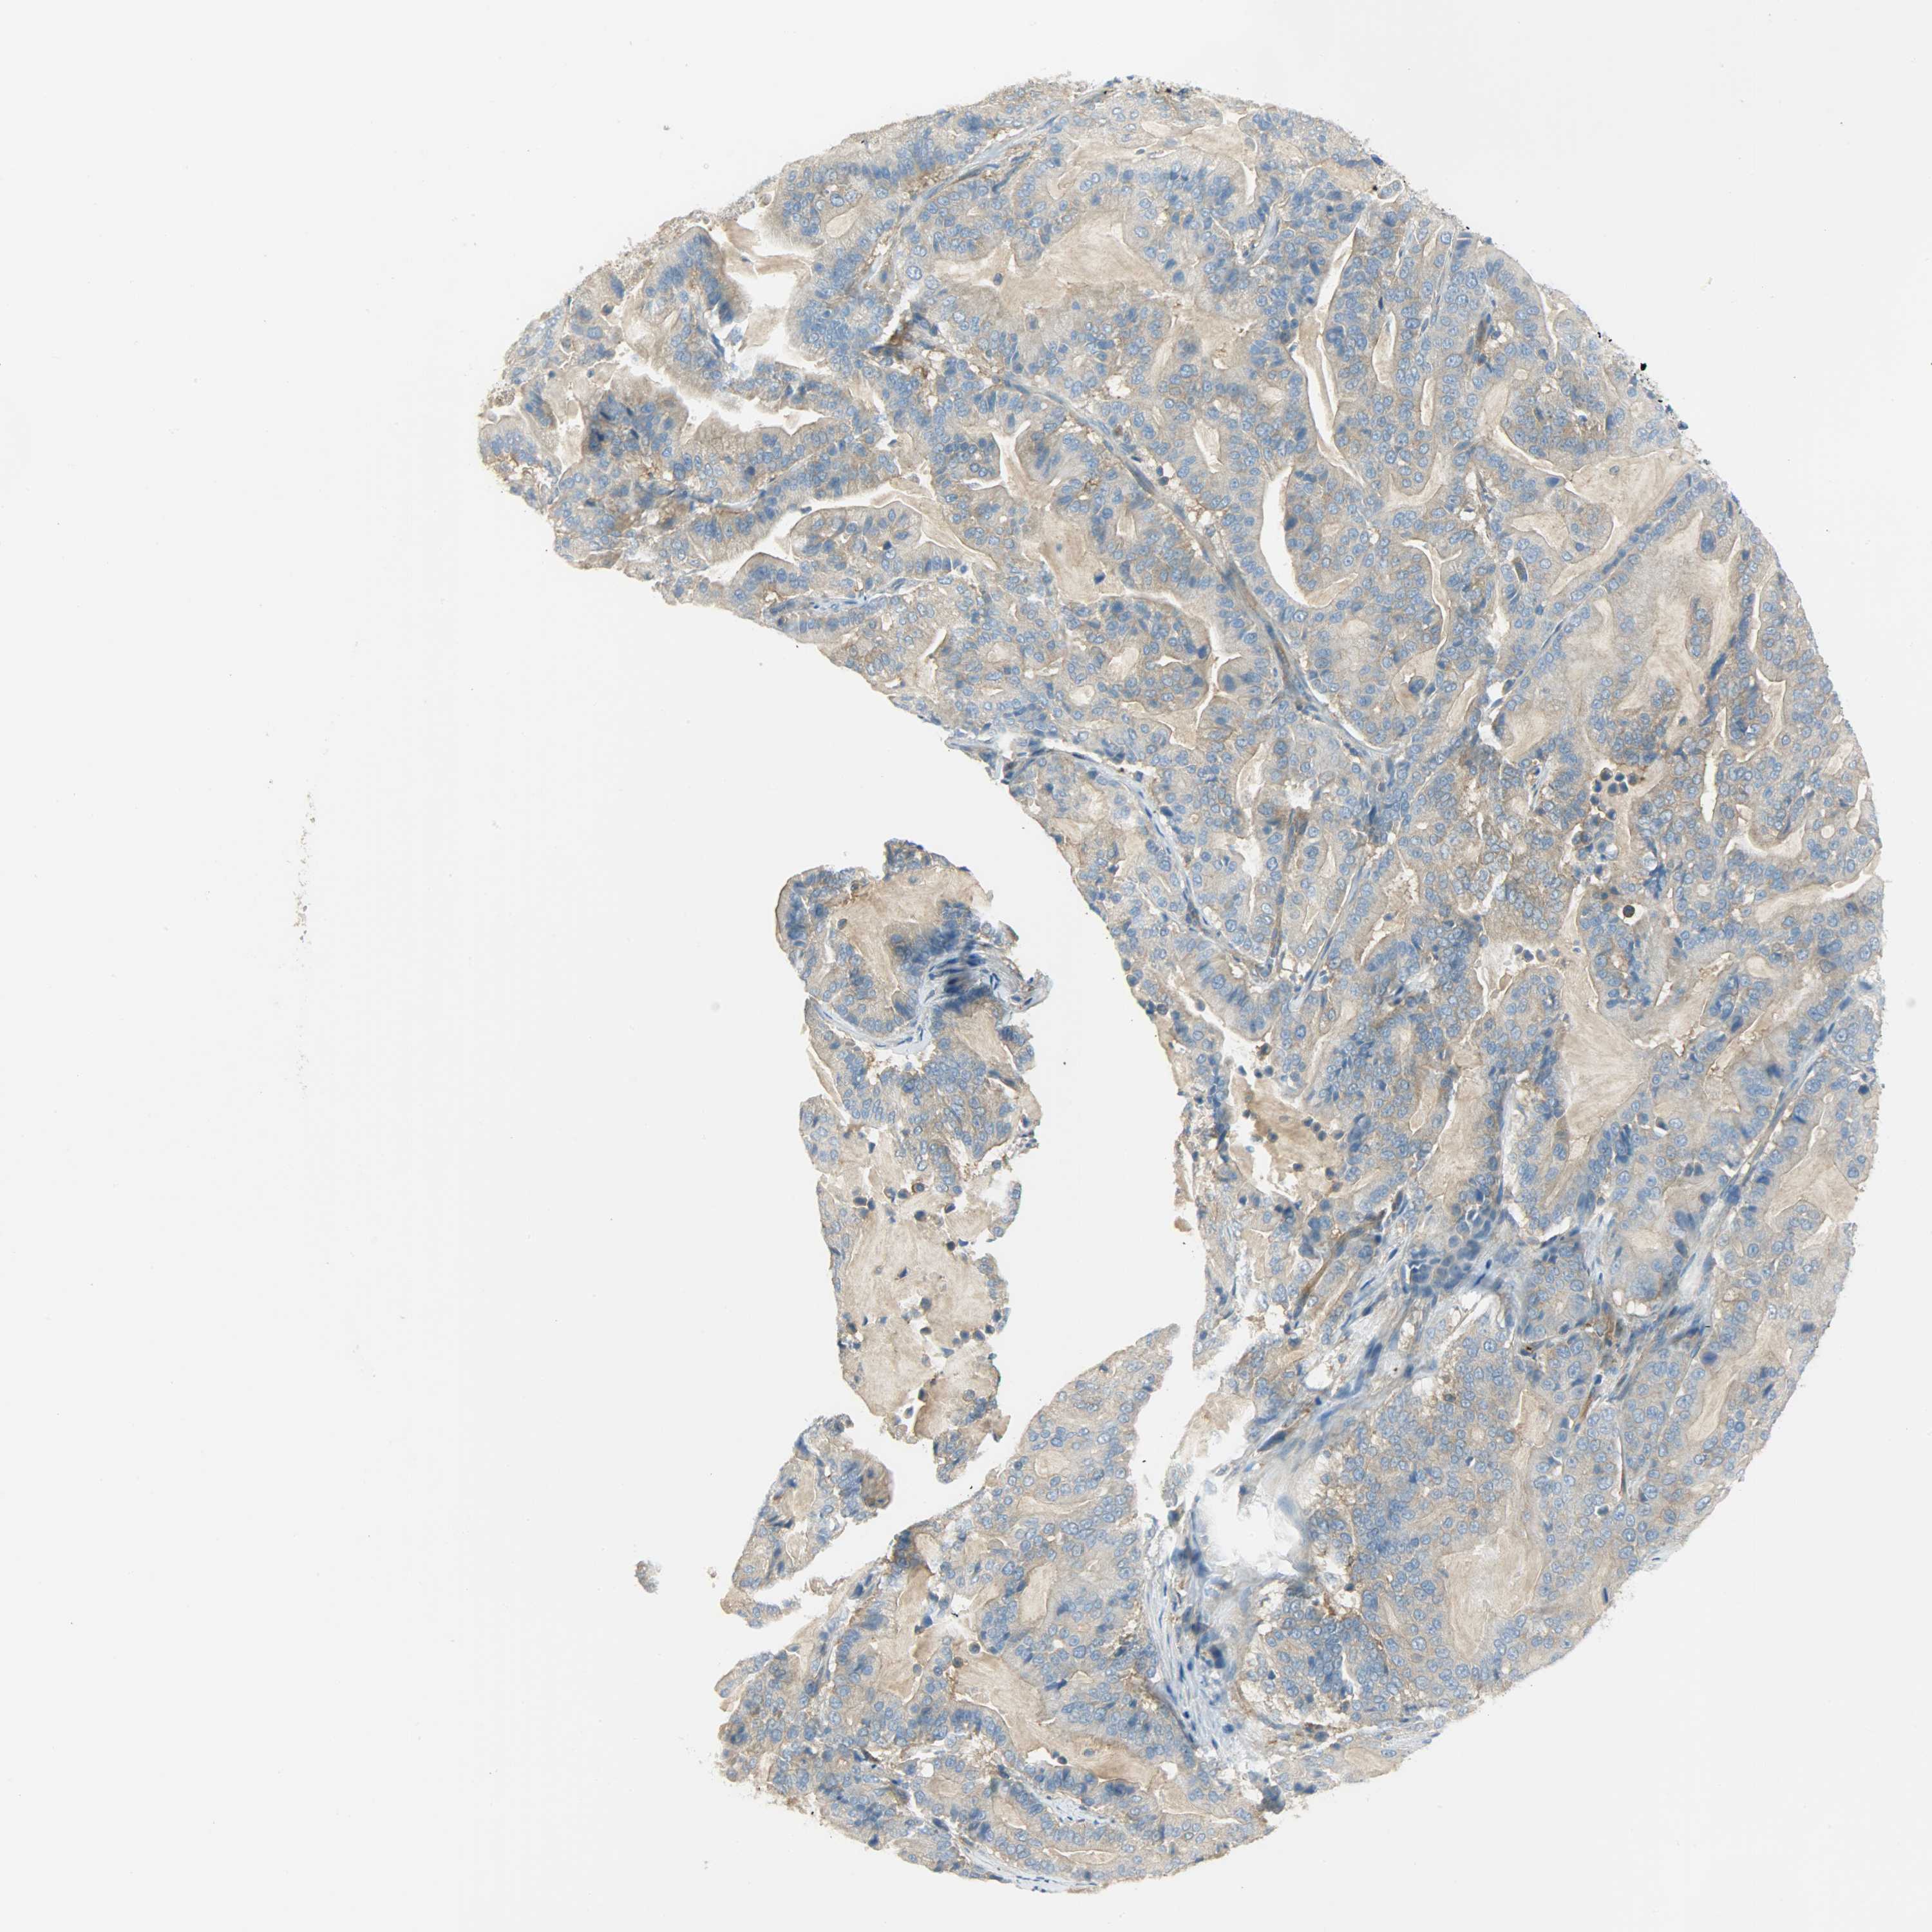

PANCREATIC CANCER - Protein expressioni

A mouse-over function shows sample information and annotation data. Click on an image to view it in a full screen mode. Samples can be filtered based on level of antibody staining by selecting one or several of the following categories: high, medium, low and not detected. The assay and annotation is described here.

Note that samples used for immunohistochemistry by the Human Protein Atlas do not correspond to samples in the TCGA dataset.

Antibody stainingi

Antibody staining in the annotated cell types in the current human tissue is reported as not detected, low, medium, or high, based on conventional immunohistochemistry profiling in selected tissues. This score is based on the combination of the staining intensity and fraction of stained cells.

Each image is clickable and will lead to virtual microscopy that enables deeper exploration of all samples and also displays staining intensity scores, fraction scores and subcellular localization as well as patient and tissue information for each sample.

Antibody HPA004926

Staining

High

Medium

Low

Not detected

Intensity

Strong

Moderate

Weak

Negative

Quantity

>75%

75%-25%

<25%

None

Location

Nuclear

Cytoplasmic/membranous

Cytoplasmic/membranous,nuclear

Adenocarcinoma, NOS

Adenocarcinoma, metastatic, NOS